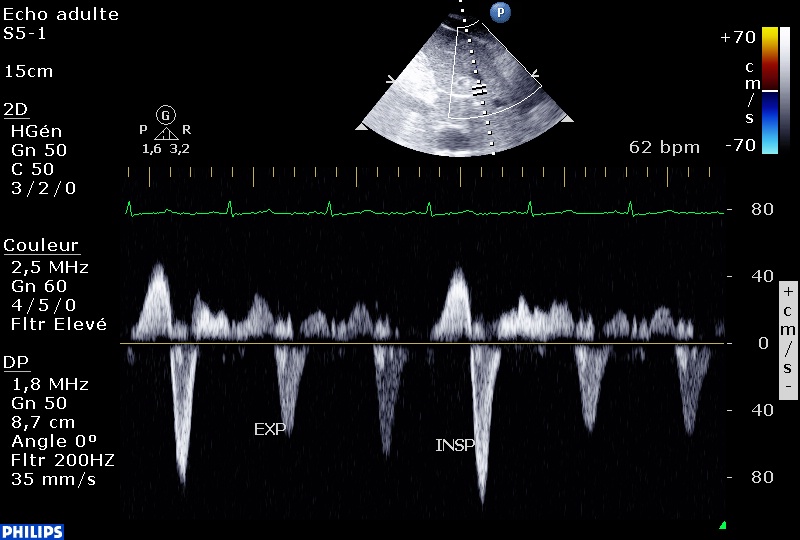

-Insuffisance tricuspide à « vélocité variable », véloce en expiration, avec un gradient VD-OD élevé traduisant une hypertension artérielle pulmonaire : en inspiration, l’IT devient massive, la vélocité devient faible,

et le reflux systolique dans les veines sus-hépatiques devient très net. Par ailleurs, la fonction systolique du VD est très abaissée.

Du fait de la grande variabilité respiratoire de la vélocité de l'IT et de l'inversion de la courbure septale, je dirais plutôt Péricardite constrictive.